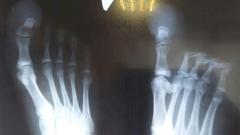

В Ивантеевскую больницу попал мужчина с открытым переломом ноги. Местный житель неудачно упал со стремянки, повредил стопу так сильно, что та вывернулась в неестественную сторону. Врачам пришлось действовать быстро.

Медики детского травматологического отделения Мытищинской городской больницы столкнулись с необычной пациенткой. У девочки был редкий диагноз — гигантизм большого пальца стопы. Он соответствовал 45 размеру ноги, а подросток носила 36.